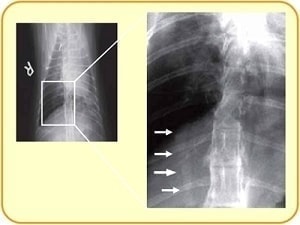

検査法③ レントゲン検査

レントゲンでフィラリアそのものは見えません。

肺や気管支の見え方、特に肺動脈の太さがヒントになります。

咳をしているネコちゃんは、レントゲンを撮ってみるといろいろ見えてくるかもしれませんね。